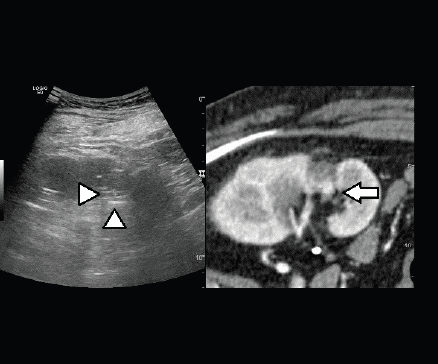

Figure 5. Fusion imaging combining real time US with CT images: CT scan shows the hypervascular nodule deeply in the scar of the previous treatment (arrow); the lesion is not clearly visible at US (heads of arrow).